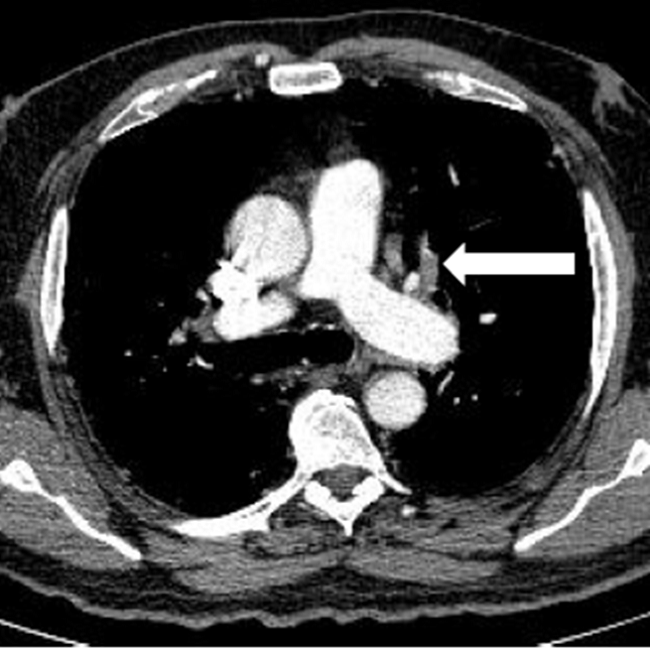

Todos los pacientes de la serie tenían hipoxia y aumento de las cifras de Dímero D con normalización en la cifra de otros parámetros típicamente alterados en esta enfermedad. De los ocho pacientes con TEP solo en dos había afectación múltiple y en ramas principales y lobares (Figura 1). En uno de los dos casos días después se confirmó la existencia de una extensa trombosis de las venas iliacas y femoral derecha como causa del TEP (Figura 2). En los otros seis casos el trombo era único y en ramas de pequeño calibre (Figura 3). En uno de los pacientes el trombo afectaba a la vena pulmonar superior izqda (Figura 4).

En la mayoría de los casos en que se vio enfermedad tromboembólica la enfermedad pulmonar era grave desde el punto de vista de la imagen,seis casos (Figura 5), en otro era moderado-grave y en un tercer paciente no había evidencia de afectación pulmonar, el paciente estaba diagnosticado de silicosis pulmonar (Figura 6) y tenía antecedentes de una neoplasia de páncreas irresecable a tratamiento con quimioterapia con fiebre y PCR positiva para COVID-19. Cuatro de los 8 pacientes con TEP tenían enfermedad muy evolucionada y grave con respiración asistida e ingreso en la UCI. Todos los pacientes tenían adenopatías mediastínicas lo que podría traducir un estado de gran inflamación (Figura 7) que podría explicar la cifra alta de Dímero D en los casos en que no existía enfermedad tromboembólica.